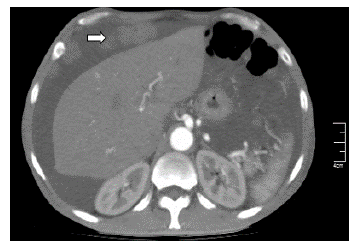

Se realizó paracentesis diagnóstica con líquido ascítico de aspecto hemático, citoquímico con leucocitos >500 células/mm3, <50 % polimorfonucleares, gradiente albúmina en plasma-líquido ascítico de 0,5 g/dL (GASA <1,1), baciloscopia negativa para bacilos ácido alcohol resistentes, reacción en cadena de polimerasa para Mycobacterium Tuberculosis (MTB) negativo, cultivo para gérmenes comunes negativo y citología negativa para células tumorales (ver Tabla 2). A pesar del reporte de citología, los hallazgos en el líquido ascítico ante la baja probabilidad de infección por MTB, sugerían carcinomatosis peritoneal, por lo que se realizó tomografía axial computarizada (TAC) de abdomen contrastada con documentación de múltiples lesiones peritoneales, lesiones líticas en huesos ilíacos de naturaleza metastásica, líquido libre en cavidad abdominal e hipertrofia prostática (ver Figura 1). Teniendo en cuenta los hallazgos imagenológicos y el grupo etario del paciente, se consideró imprescindible descartar CaP, complementándose el examen físico con tacto rectal con hallazgo de próstata fija, pétrea, recesos bilaterales comprometidos. Antígeno específico prostático con resultado total de 1090 ng/ mL. Por lo cual, se realizó diagnóstico clínico de CaP con más probable compromiso metastásico óseo; sin embargo, sin certeza de secundarismo peritoneal dado el comportamiento poco frecuente de diseminación peritoneal del CaP. Se complementó estudio con esofagogastroduodenoscopia y colonoscopia total dentro de la normalidad, decidiéndose realizar biopsia de lesiones peritoneales por laparoscopia, con hallazgos de múltiples siembras en grasa peritoneal sin adenopatías visibles, con reporte histopatológico que confirmó CP por adenocarcinoma pobremente diferenciado de origen prostático, T4N0M1, estadio IVb, Gleason X (Ver figura 2 a,b). Citología de líquido peritoneal de muestra obtenida durante procedimiento quirúrgico con hallazgo de grupos de células atípicas con núcleos hipercromáticos compatible con carcinoma metastásico. Dentro de los estudios de extensión se realizó gammagrafía ósea con hallazgo de múltiples focos de hipercaptación anormal en cráneo, escápula izquierda, arcos costales de manera difusa así como en T7 a T10, L1 a L3 y tercio proximal de fémur derecho. Se realizó bloqueo hormonal mediante orquiectomía bilateral paliativa ante estadificación tumoral, sin complicaciones. Servicio de urología oncológica dio egreso hospitalario con orden de cita prioritaria por su servicio con control sérico de PSA y testosterona total. A la fecha completa 24 meses vivo en controles por urología oncológica extrainstitucional, recibiendo radioterapia y bloqueo androgénico completo con inhibición de la señalización de los receptores androgénicos (enzalutamida).

Figura 1 TAC toracoabdominal con doble contraste oral/ intravenoso. Flecha señala en corte axial una de las múltiples lesiones peritoneales, compatibles con siembras por carcinomatosis peritoneal.